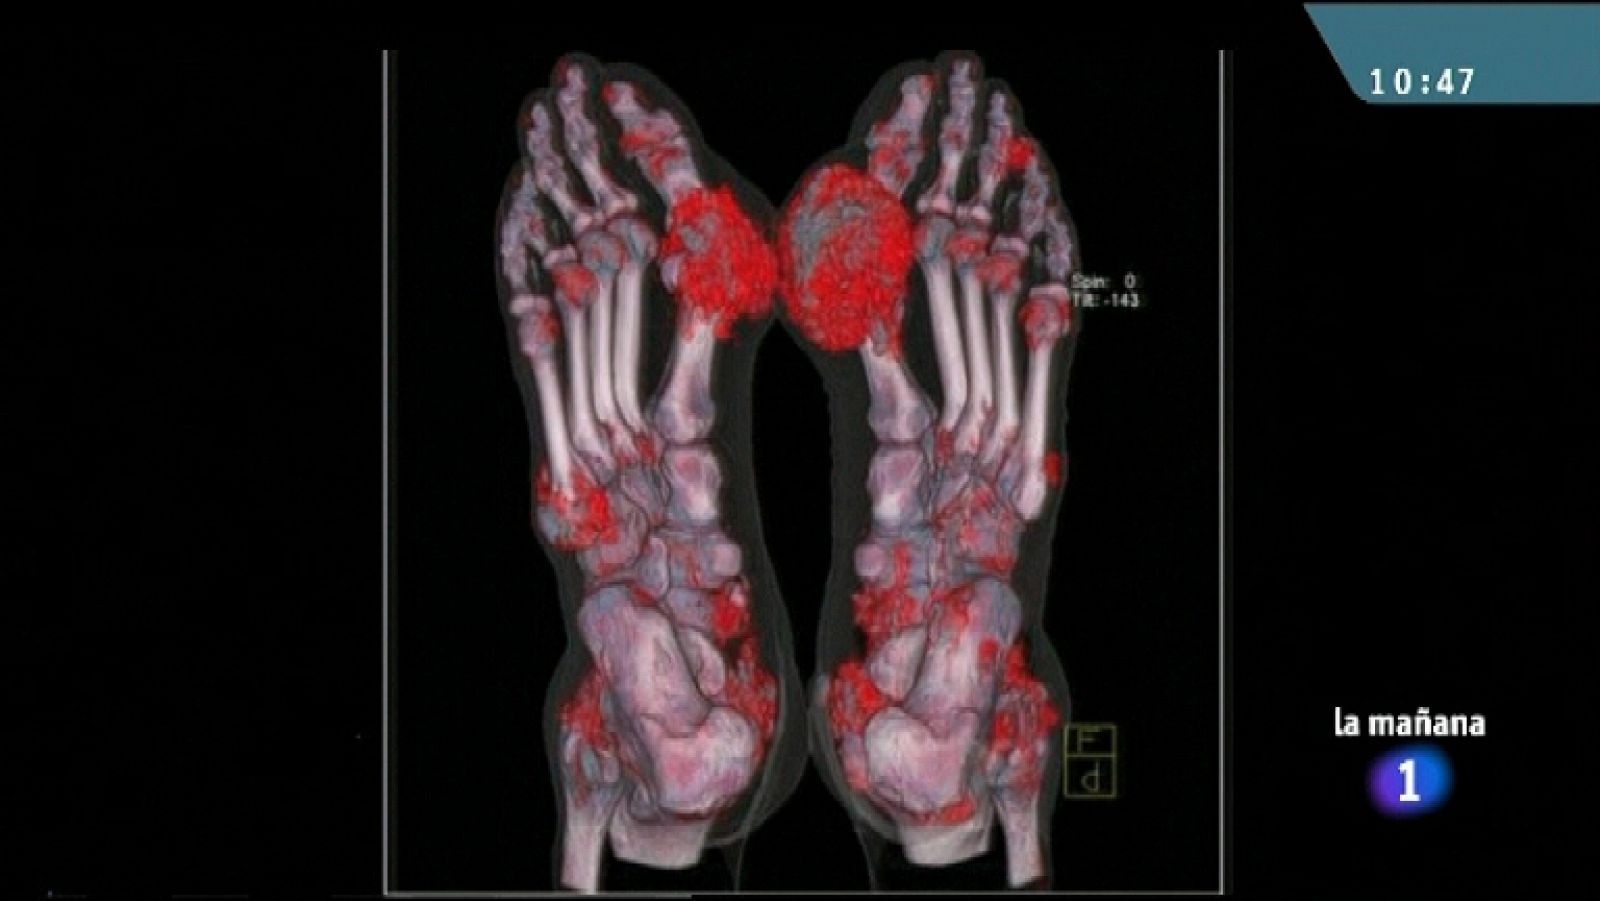

Ácido úrico al final del año

Ácido úrico al final del año